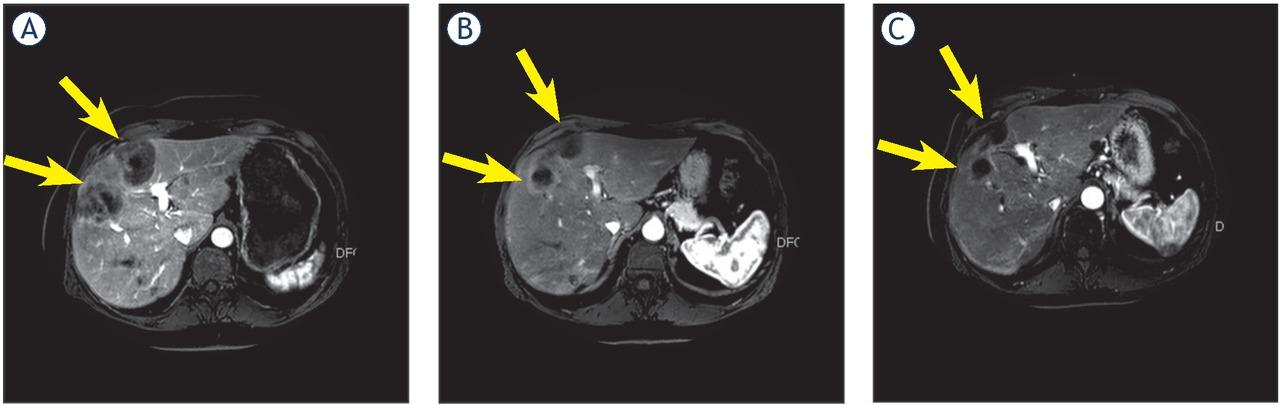

Response evaluation of the liver after 6 to 8 weeks after 90Y treatment (n = 16) revealed PR in 10 patients and SD in 6 patients (Figure 2). Extra hepatic response evaluation showed PD in 5 patients and SD in 11 patients. Additional hepatic response of MMC infusion after 90Y treatment was PR in 4/12 patient, SD in 5/12 patients and PD in 3/12 patients.

Hepatic response on magnetic resonance imaging (MRI) before 90Y treatment (A), after 90Y treatment (B) and after 2 cycles of MMC infusion (C). C is a partial response relative to A. Arrows indicate the liver metastases.